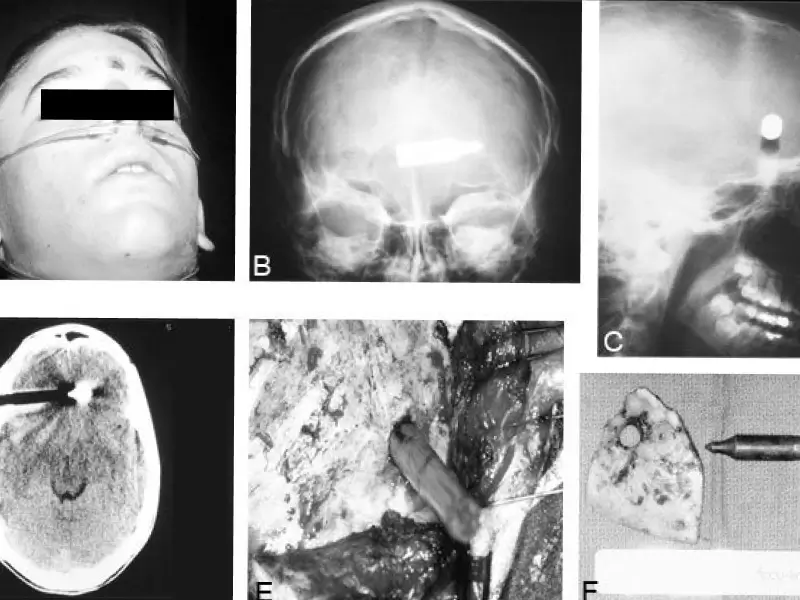

X-ray imaging reveals the trajectory of a crossbow bolt

In August 2025, police in Ancona, Italy, were dispatched to perform a routine welfare check on a 64-year-old man. What they discovered inside the apartment was anything but routine.

The man was found lying in his bed with the end of a crossbow bolt embedded in his forehead. Despite the severity of the injury, he was still alive.

He was rushed to hospital, where doctors determined that he had survived for at least two days in this condition. Medical staff reported that he was conscious but communicating incoherently and had not eaten during that time.

If the arrow had penetrated just one millimeter deeper, the injury would have been instantly lethal.

Emergency neurosurgery was performed successfully to remove the bolt. While the operation itself went well, doctors described the man’s condition afterward as serious, and no further public updates on his recovery have been released.